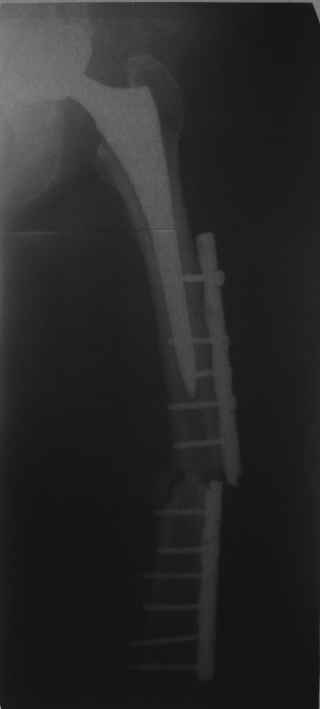

Дорогой Александр Николаевич! Спасибо, что держите всех нас в курсе.

Сейчас опорную нагрузку на бедро берет на себя система от бедренного компонента эндопротеза до проксимального винта в интрамедуллярном гвозде. Свидетельство тому - реакция кортикала утолщением вокруг того самого винта. Таким образом вся кость от верхушки б.вертела до проксимального винта не испытывает физиологической осевой нагрузки. Результатом этого могут стать следующие последствия друг друга не исключающие: 1) все будет хорошо до перелома опорной системы по винту(ам) или в месте соединения штифта с ножкой или еще где-либо, 2) исключенная из-под нагрузки кость будет терять в количестве и качестве, что не очень (или очень не) хорошо для возможных будущих ревизий (тьфу-тьфу!!!).

Другой вариант перенести нагрузку на кость, "боем" проверив фиксацию ножки. Динамически заперев винт на 5мм ниже проксимального края овального отверстия. Статические винты отпереть, пациенту рекомендовать постепенно возрастающую дозированную нагрузку до полной в течение месяца. Хотя срок интеграции бесцементника считается 3 месяца(так пишут в руководствах и рекомендациях), если допустить, что ножка не интегрировалась. Появление клиники или проседание ножки по рентгенограмме даст ответ на счет того произошла ли интеграция или нет. С другой стороны проседание на 5 мм вряд ли приведет к чему либо серьезному, и если интеграции нет - рассматривать вопрос о ревизии. Если ножка интегрировалась, стрежень не удалять - для избежания перипротезных переломов.

Обещанные ранее снимки Заранее спасибо.